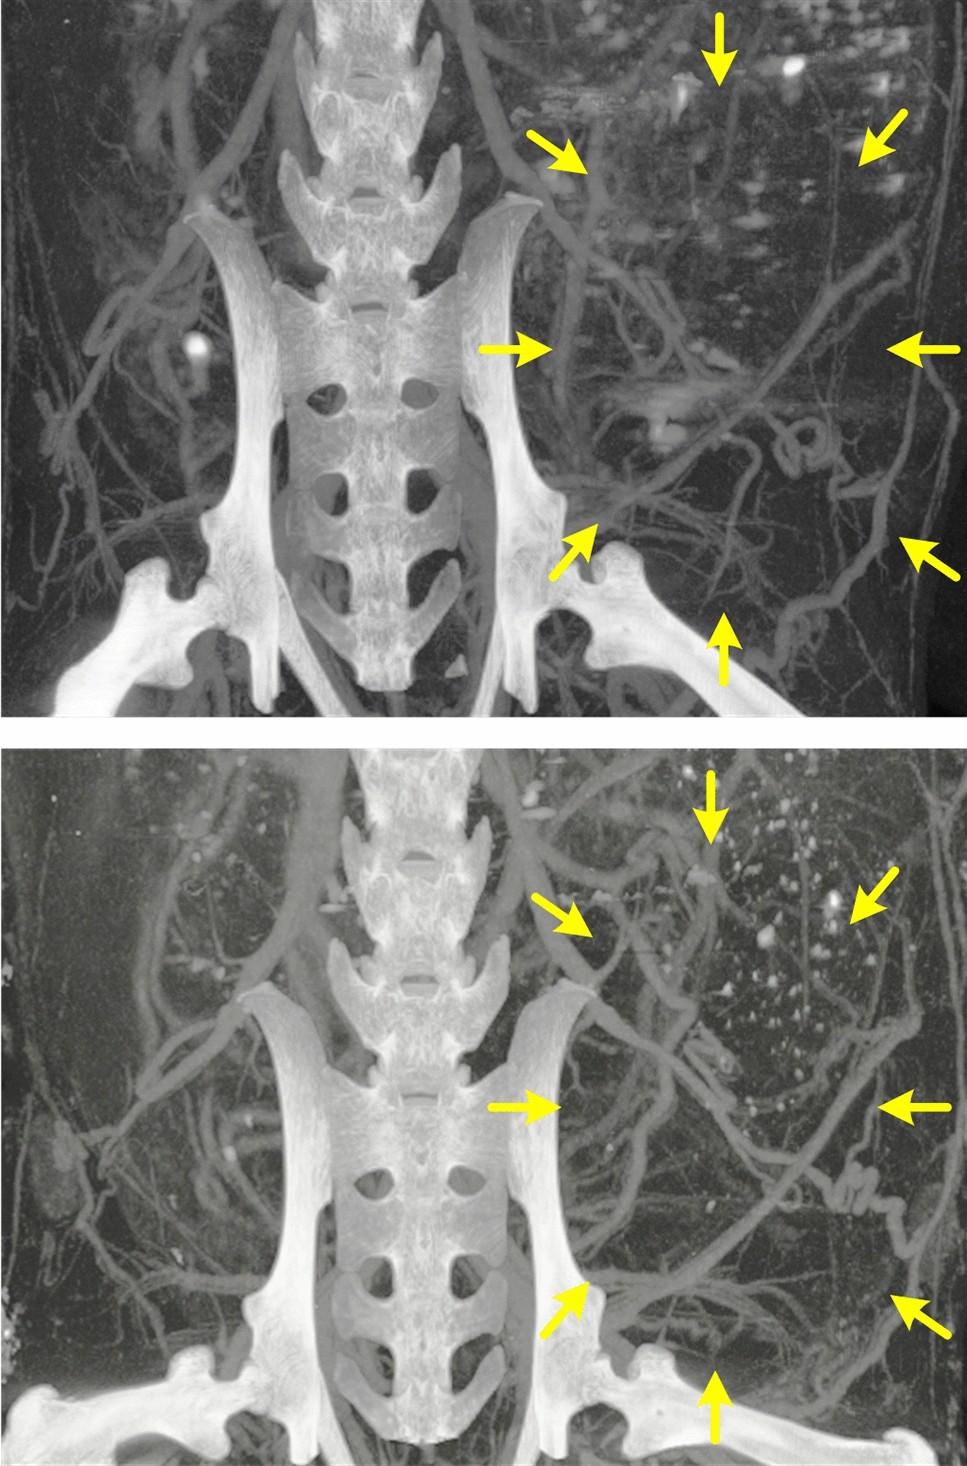

Figure 5

Series of preclinical in vivo contrast-enhanced microscale computed tomography (microCT) images of an aggressive breast cancer (yellow arrows) acquired in the same animal at reference baseline (top) and 2Â wks (bottom).